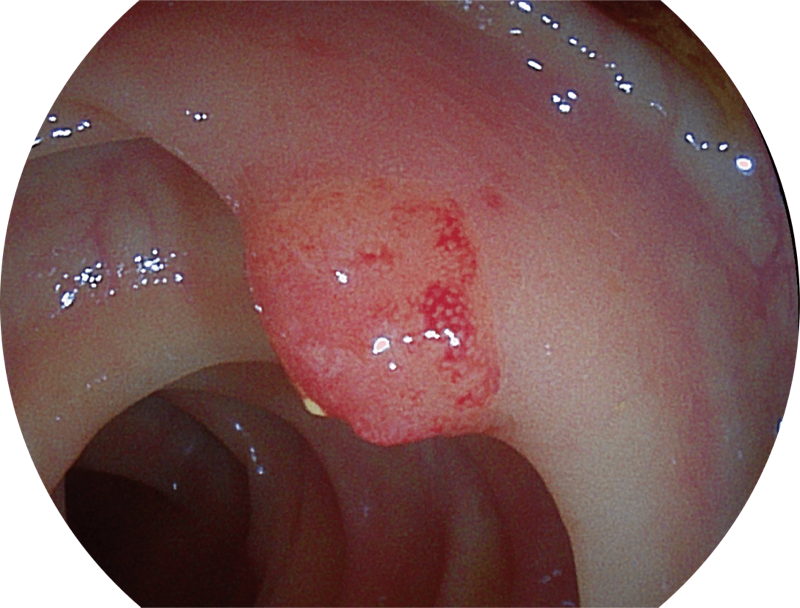

能够凸显黏膜浅层和中层血管轮廓,适用于中、远景观察下的病灶识别和早癌筛查。

SFI图像